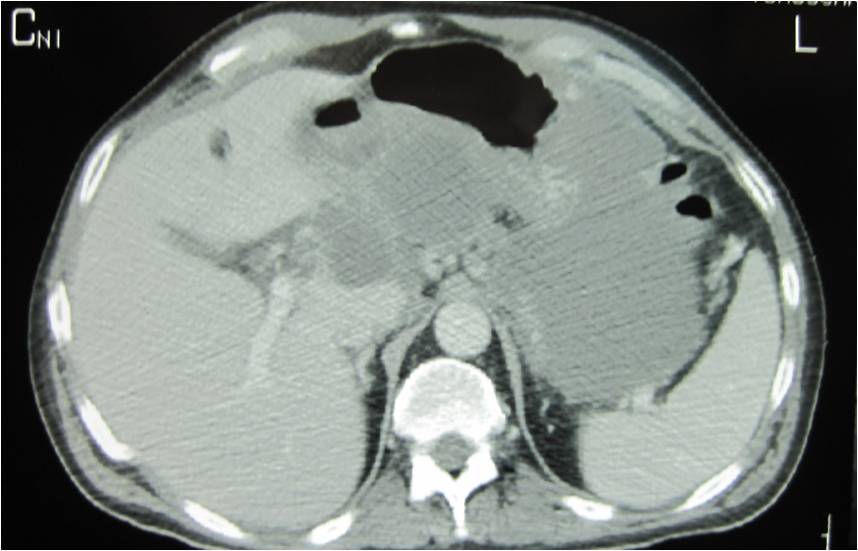

- Abscess post right hemicolectomy

- Successful placement and drainage